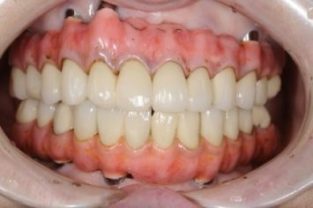

| 主訴 | 歯がグラグラで噛むことができない。インプラントをして欲しい。 |

| 治療内容 | 歯周病で骨の吸収が重度で保存不能なため抜歯、仮の入れ歯を作り、6ヶ月の抜歯窩の治療の後に、インプラントのCTによる診査診断を行い、下顎に6本インプラント埋入と同時に仮歯を入れる。その後、上顎は8本のインプラント埋入と同時に仮歯を入れる。左右上6はソケットリフトによる上顎洞拳上術を行う。その後免荷期間6ヶ月待ってセラミックを用いた上部構造作製、装着しメンテナンスに移行する。 |

| 治療費 | 9,000,000円(税込) |

| 治療期間 | 2年3ヶ月 |

| 治療回数 | 90回 |

| 想定されたリスク | 重度の歯周病により無歯顎になったため、プラークコントロール不良による、術後のインプラント周囲炎が懸念される。歯冠の部分はセラミックなため欠ける可能性がある。 |